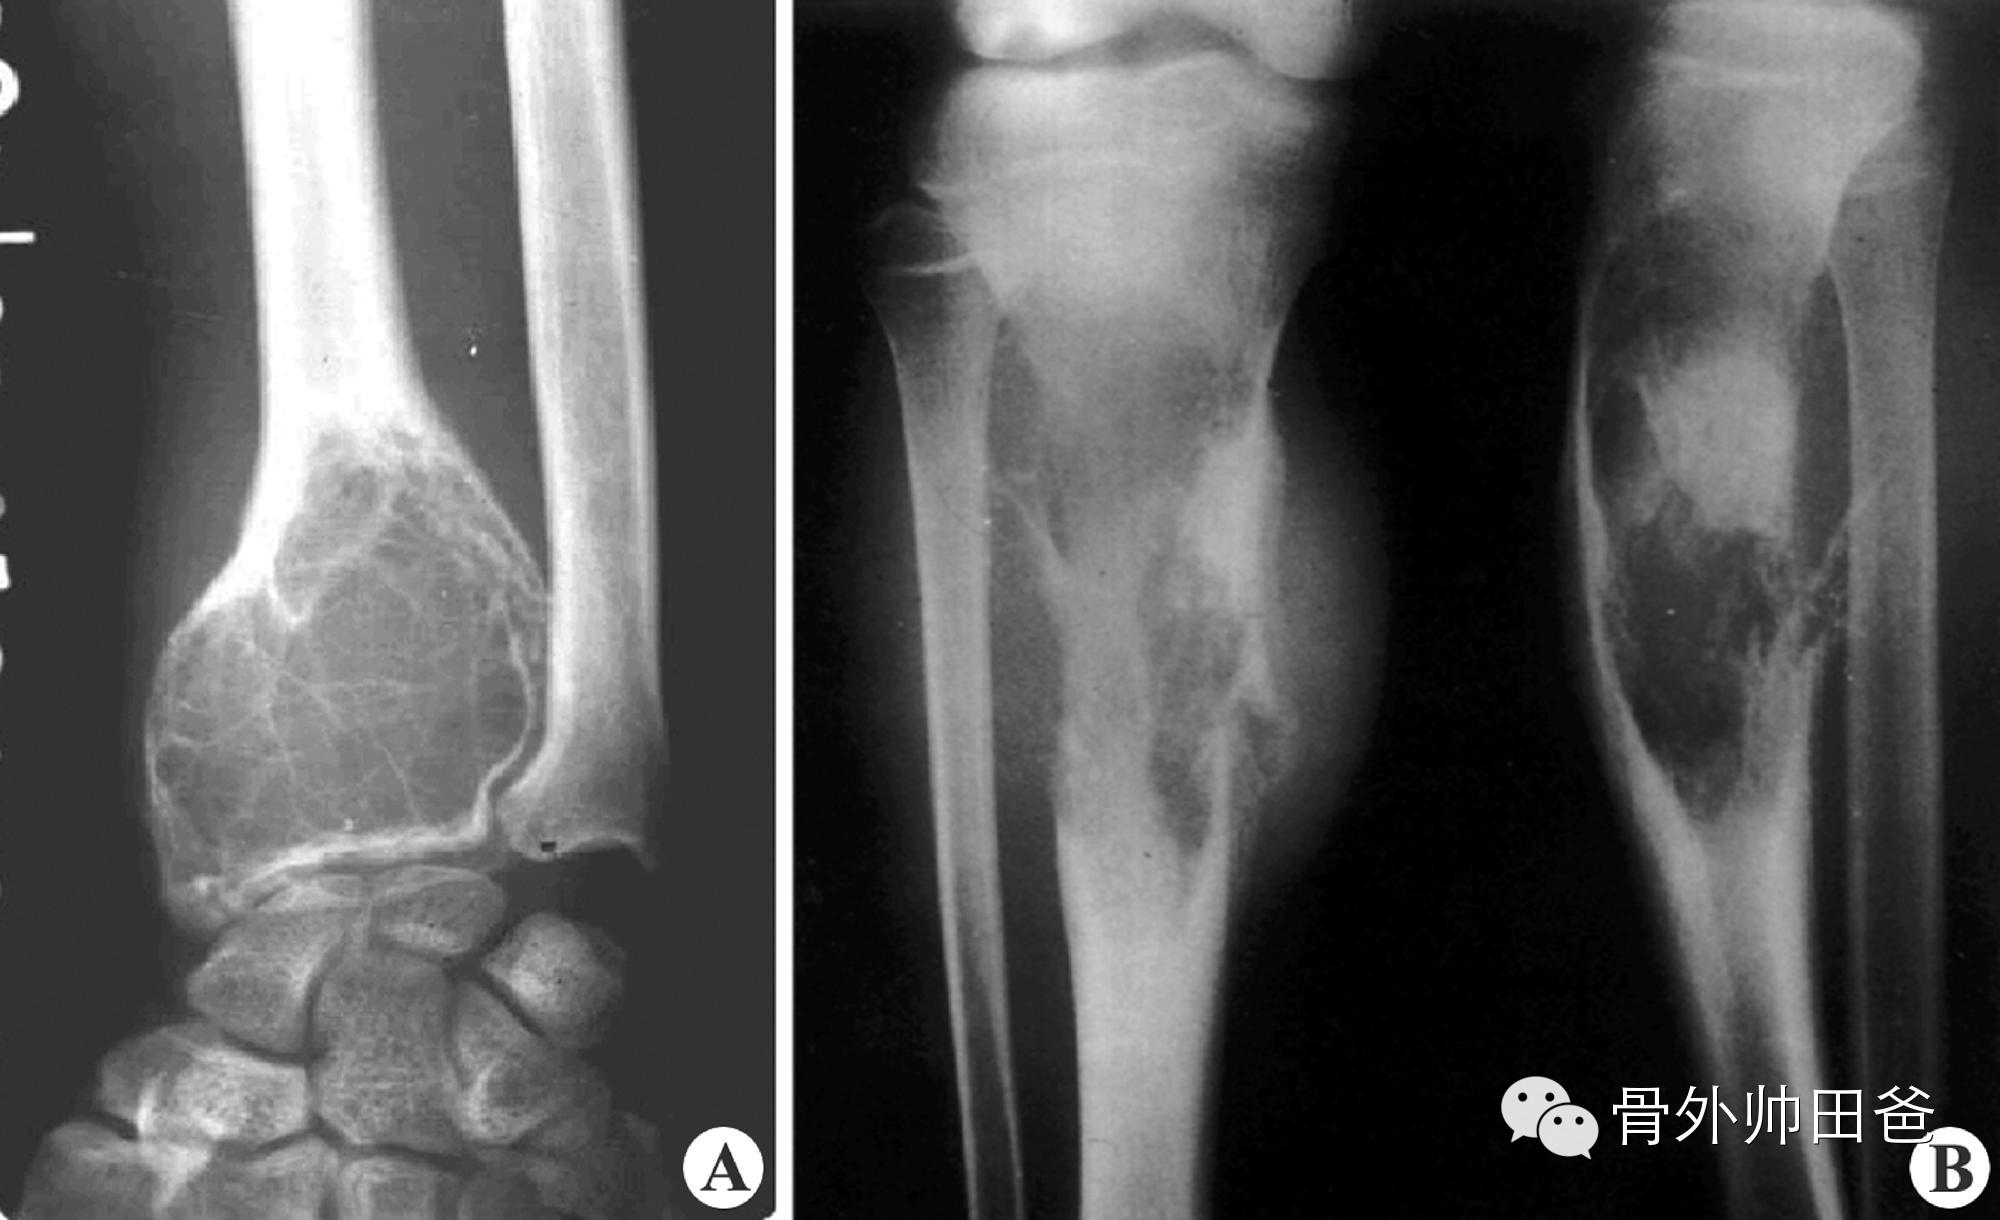

骨关节肿瘤:各种骨的良恶性肿瘤,均可引起关节疼痛,关节活动障碍。